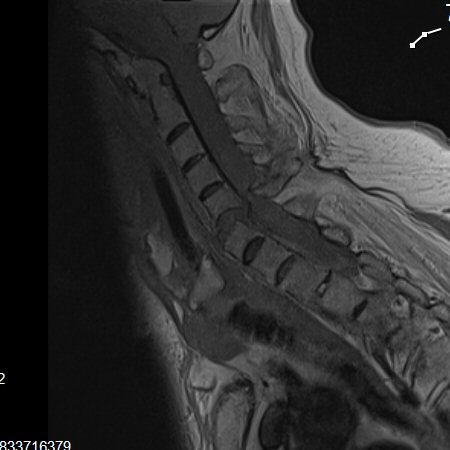

Notera att vid Bechterews sjukdom eller DISH-förändringar så blir frakturer ofta instabila. MR-undersökning krävs ofta inför operationsbeslut.

Instabil fraktur mellan C5 och C6 i Bechterew-rygg där ryggmärgen kapats nästan helt.